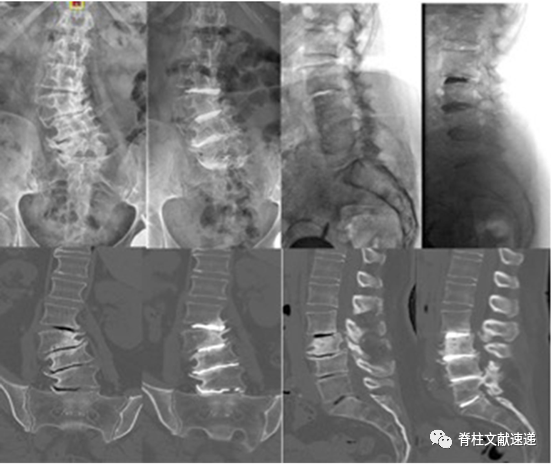

患者术前需完善影像学检查(X线、CT、MRI)。X线可显示站立和卧位时椎间盘高度存在明显差异,CT结果中同样可以观察到这种现象,站立和卧位时X线及CT结果显示椎间隙高度变化的情况称之为手风琴现象(如下图),提示椎体存在不稳定情况。

图注:患者术前影响结果观察到手风琴现象,PCD术后冠状位及矢状位畸形均得到部分缓解;